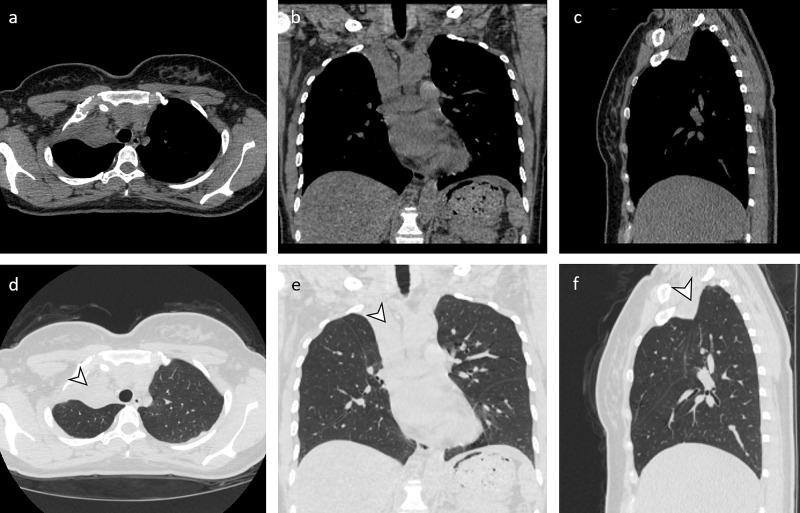

Pulmonary tuberculosis is common worldwide, and many of these patients develop endobronchial tuberculosis (EBTB). Bronchostenosis is a known complication of EBTB though most patients with endobronchial stenosis do not develop severe bronchostenosis or occlusion. We present a rare case of a patient with a right upper lobe bronchus occlusion and a history of tuberculosis.

肺结核在全球范围内都很常见,其中许多患者会发展为支气管内膜结核(EBTB)。支气管狭窄是EBTB的一种已知并发症,尽管大多数支气管内膜狭窄患者不会发展为严重的支气管狭窄或阻塞。我们报告一例罕见病例,该患者右肺上叶支气管闭塞且有结核病史。